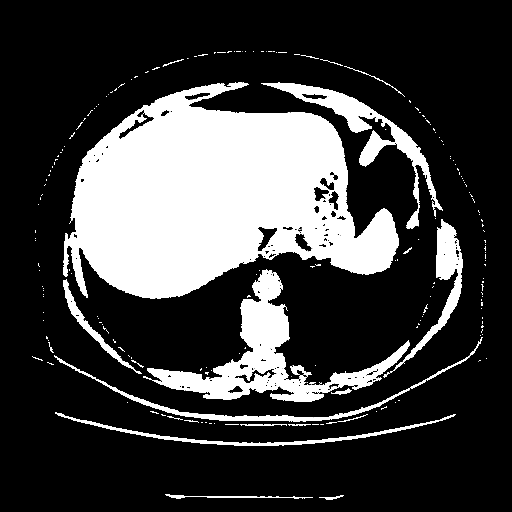

Generated VENOUS CT scan (A→B translation)

Full window (WL 1023.5, WW 4095 β†’ Low βˆ’1024, High +3071)

Actual HU range: [-1024.0, 3071.0]